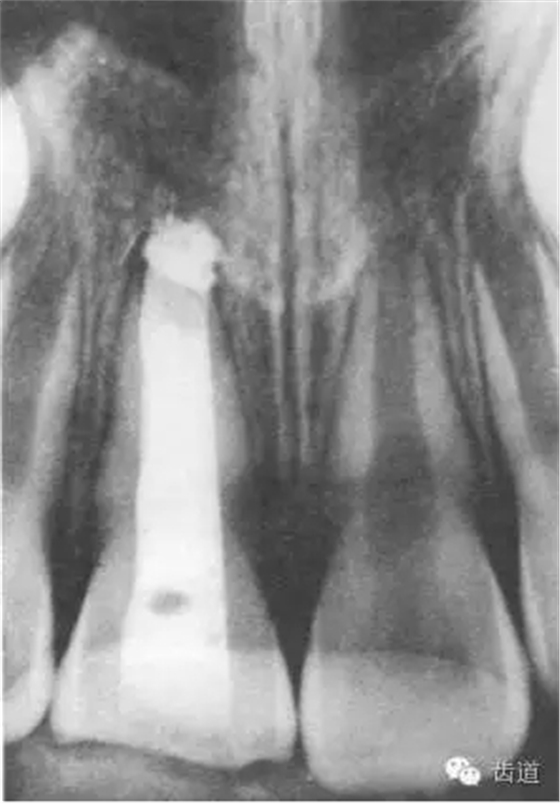

3個(gè)月左右在X線片上可觀察到修復(fù)性牙本質(zhì)層的出現(xiàn), 術(shù)后6個(gè)月左右,常可觀察到連續(xù)的有一定厚度的修復(fù)性牙本質(zhì)層; 修復(fù)性牙本質(zhì)層的出現(xiàn),是間接牙髓治療成功的重要指征。

術(shù)后當(dāng)天

術(shù)后五個(gè)月

術(shù)后一個(gè)月

術(shù)后11個(gè)月